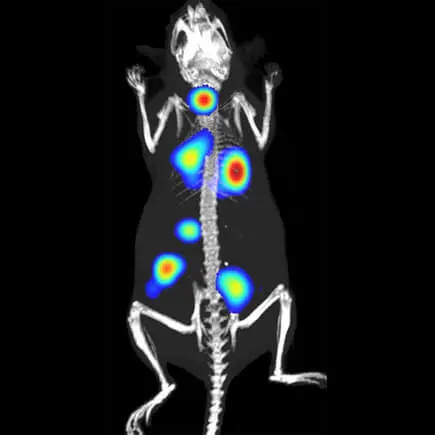

Metastaza nowotworu, znakowanie bioluminescencyjne: IVIS Spectrum CT